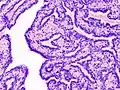

Intraductal papilloma

Histopathology of intraductal papilloma of the breast by excisional biopsy. Immunostaining for p63 protein.